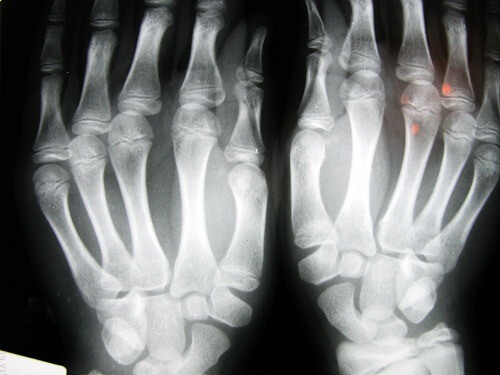

2. Le risque d’ostéoarthrite liés aux doigts

Une étude réalisée par l’Université de Nottingham, au Royaume-Uni, a pu déterminer que les personnes qui ont l’index plus court que la normale ont un risque de développer des problèmes osseux, comme l’ostéoarthrite, plus élevés que la moyenne.

Ce problème est à mettre en relation avec un manque d’œstrogènes. Et avec une activité physique faible. Deux éléments qui concernent souvent les femmes.